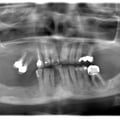

Лікування карієсу дистопованого 48 зуба не є вирішенням даної патології. Дистопія зуба мудрості провокує виникнення карієсу 47 зуба. Даний зуб має бути видалений